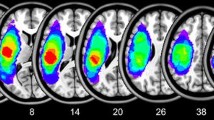

18FDG-PET analysis

18FDG-PET results

18FDG-PET analysis revealed regions with statistically significant decreased metabolism compared to a control group in the four patients (Table S6 and Fig. 4). P1 showed significantly lower metabolic activity than controls in the left anterior insula within a cluster extending subcortically until the putamen. Reduced activity was also found in the left inferior and superior parietal cortices, and in the bilateral inferior temporal gyrus, MTG, and STG. P2 showed hypometabolic activity in the left MTG and SMG, AG, insula, and precuneus. P3 had decreased metabolic activity in the left IFG, MFG, precentral gyrus, MTG and inferior temporal gyrus. Finally, P4 showed hypometabolic activity in the SMA, SMG, IFG pTr, superior parietal cortex, and MTG. P2, P3, and P4 did not show hypometabolic activity in the right hemisphere. No hypermetabolic activity was found for any of the participants at the selected statistical threshold (i.e., p < 0.05 FWE corrected).

18FDG-PET results. 18FDG-PET analyses revealed areas of hypometabolism in the four patients. Compared to a group of 25 healthy controls, hypometabolic areas were found in the perisylvian (purple color) and extrasylvian areas (blue color) in perilesional regions but also in distant areas, especially in P1 and P2. A statistical threshold of p < 0.05 (FWE corrected) was applied. No hypermetabolic areas were found at this statistical threshold. L left; R right